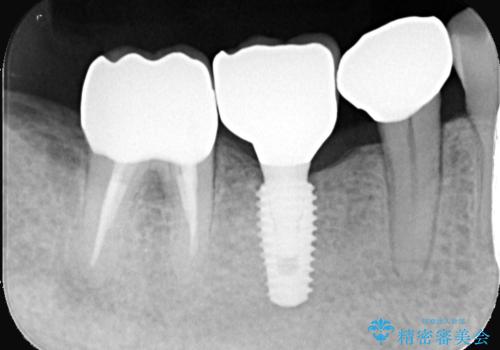

対合歯との咬合関係において、右下7番目と6番目の被せものの連結部がたわみやすい環境にあったため、ブリッジの新製ではなくインプラント治療を行いすべての歯を単冠仕上げとすることにしました。

何度も右下6、7間でブリッジが折れてしまうとのことでした。対合歯とブリッジの連結部が強く当たりたわみやすい状態でした。破折しずらい金属を使用したブリッジの選択もありましたが、支台歯(右下7)が失活歯場合、破折リスクが高く、破折してしまった場合にまたブリッジを外しての再治療になってしまう可能性を説明したところ、全て単冠仕上げとできるインプラント治療を希望されました。

右下5番のクラウンは、ブリッジを切断しそのまま使用していただいています。